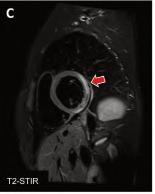

Lamiocarditisesunainflamacióndel músculodelcorazón(miocardio). Puedesercausadaporvariasenferme‐dades,infeccionesviralesobacterianas,tra‐stornosautoinmunitarios,exposiciónatoxi‐nas,entreotrosfactores.

¿CUÁLESSURELACIÓNCONLACOVID-19?

EnelcontextodelapandemiadeCOVID-19,se hainformadodecasosdemiocarditisaso‐ciadosalainfecciónporelvirusSARS-CoV-2. Secreequeestopuededebersealarespuesta inmunitariadelcuerpoalainfección,que puedeprovocarinflamaciónenvarios órganos,incluidoelcorazón.

Tambiénsehainformadodecasosmuyraros demiocarditisdespuésdelavacunación contraCOVID-19,especialmenteenpersonas jóvenesdespuésderecibirlavacunadeARNm (Pfizer-BioNTechyModerna).

Aunquesenecesitamásinvestigaciónpara comprendercompletamentelarelaciónentrela miocarditisylavacunaCOVID-19,losexpertos hanseñaladoquelosbeneficiosdelavacu‐

nacióncontraCOVID-19superanconcreces losriesgosdeefectossecundariosgraves.

Esimportantedestacarquelamiocarditises unaafeccióngravequepuedeponerenpeligro lavida,pueslamortalidadpuedellegaraserha‐stadel20%encasodenosertratadaatiempo, yelmétodonoinvasivomásadecuadoparasu diagnósticoeslacardiorresonancia.

Siexperimentasíntomascomodolorenel pecho,dificultadpararespirar,palpitaciones ofatigadespuésdelavacunaciónolainfec‐ciónporCOVID-19,debebuscaratenciónmé‐dicadeinmediato.

¿Porquéestáasociadaaunainfección ovacunadeCovid,SARS-CoV-2?Resonanciamagnéticaybiopsiaendomiocárdica